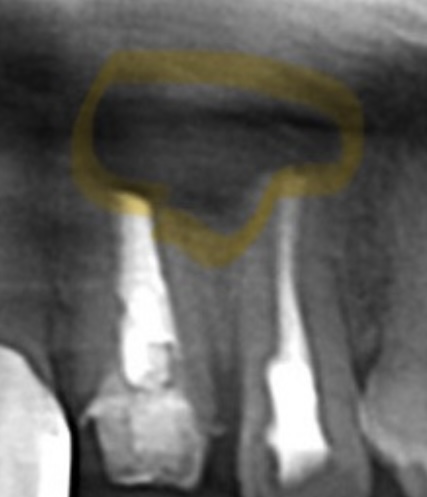

手術当日 術後レントゲン

| 主訴 | 左上前歯が痛くて歯茎が腫れている。3年ほど前に神経治療をした。 |

|---|---|

| 所見 | パノラマレントゲンにて左上1番2番に透過像が確認され、根尖相当部歯肉にフィステルあり。また排膿も伴う。打診痛、自発痛あり。 |

| 診断 | 左上1.2部 慢性根尖性歯周炎 |

| 治療内容 | 感染根管処置を行い根管内を無菌化し、貼薬を行った後、マイクロスコープ下にて歯根端切除術を行った。 |

| 治療後経過 | 6ヶ月経過 パノラマレントゲンにて患部の骨の回復が見られた。打診痛、自発痛共に無く経過良好。 |

| 治療期間 | 1ヶ月 |

| 治療費用 | 100,000円 自由診療 |

| リスク・副作用 | 病変が消失しないことがあります。 |